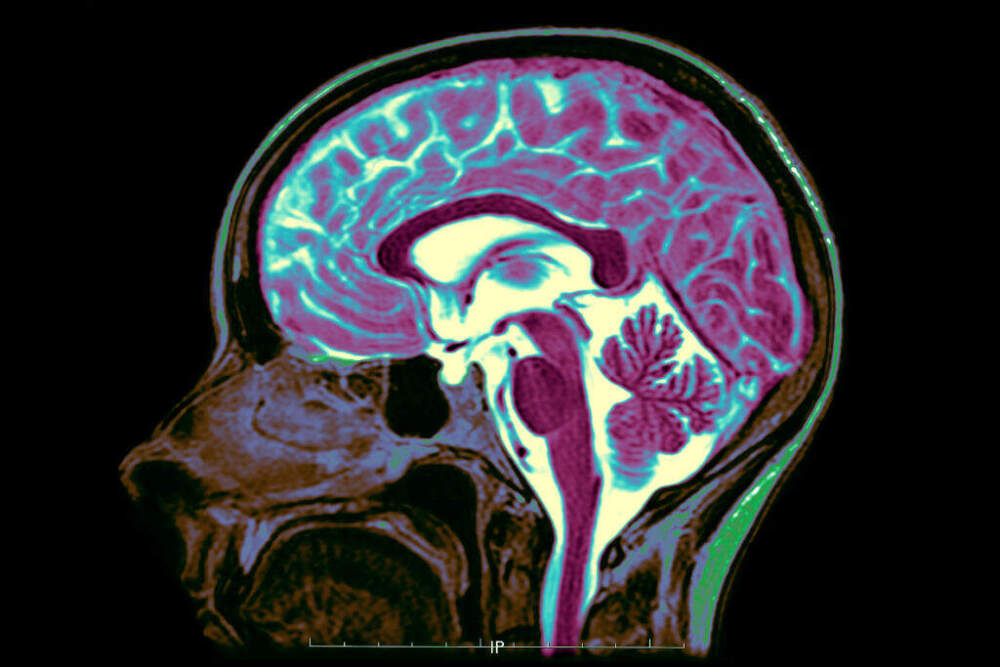

The brain is the organ that makes us who we are. It’s our conduit between reality and thought. But somehow, we’ve only scratched the surface in understanding how the brain actually works.

KANWISHER: Okay. I guess we could break it down into three main kind of chunks. There's all the subcortical stuff where you have these nuclei that do different things, and they do some pretty basic survival things like controlled breathing rate and digestion and stuff like that.

They also do some more important things like control your habits and your ability to learn. And then sitting on top of that is this massive bundle of fibers, millions of miles of fibers. You can think of it as a wires of each neuron has a wire coming out of it that connects it to other neurons.

And so about 40% of the volume of your brain is white matter, or just wires.

KANWISHER: And then sitting on the top, the outer surface is called the cortex. And it's the size and thickness of a large pizza.

And so if you imagine taking a large pizza and trying to fit it in your head, you have to crumple it up. That's why the brain is all folded, because its native structure is this surface. And to fit that surface in your head, you have to crumple it up.

KANWISHER: That's where most of the conscious thinking, perception, action, planning, all the stuff that we think of as thoughts and intelligent behavior is constructed mostly in the cortex.